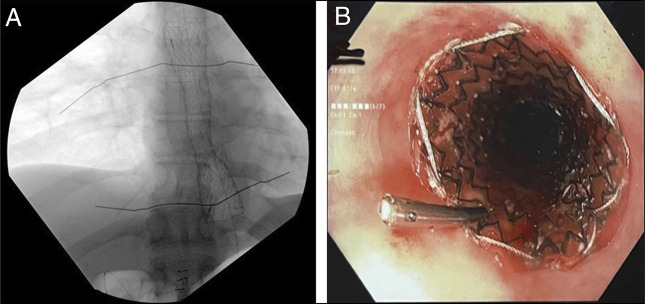

The combined antegrade and retrograde endoscopic rendezvous technique effectively restores patency for esophageal short-segment obstructing strictures (<3 cm). However, long-segment strictures typically require complex surgery, with endoscopic management rarely reported. We report a 44-year-old man with a 9 cm esophageal obstruction due to peptic stricture who was at high risk of esophageal resection due to severe cardiac disease and prior abdominal surgeries. He underwent successful recanalization using a rendezvous technique. Serial dilations with subsequent esophageal stenting restored luminal patency. This case highlights the feasibility of an endoscopic approach as a safe and effective alternative to surgery in long-segment peptic strictures.

Abstract Image